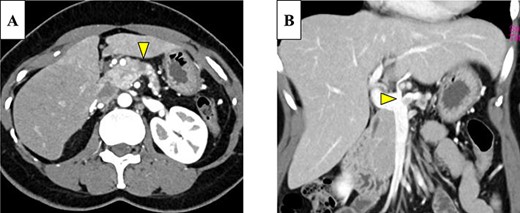

Abdominal-enhanced computed tomography (CT) revealed a low-density pancreatic body tumor of 25 mm in diameter, which was close to the gastroduodenal artery (GDA), and was accompanied by atrophy of the distal pancreatic parenchyma and dilation of the upstream MPD (Fig. 1A). Moreover, CT imaging of the portal phase revealed a filling defect within the splenic vein where it was in contact with the tumor (Fig. 1B). On magnetic resonance imaging, the tumor appeared as an area of signal hyperintensity on T2-weighted and diffusion-weighted images (Fig. 2A and B). On positron emission tomography-CT scan, the tumor exhibited greater uptake of 18F-fluorodeoxyglucose (Fig. 3). Although a definitive preoperative diagnosis could not be made, we suspected pancreatic ductal adenocarcinoma, and distal pancreatectomy with lymph node dissection was scheduled, without neoadjuvant chemotherapy, after obtaining consent from the patient. The pancreas was divided along the left edge of the GDA after mobilization of the artery; however, pathological examination of a frozen section of the pancreas stump was positive for PNET, and therefore a total pancreatectomy was performed (Fig. 4). The duration of surgery was 610 min, the intraoperative blood loss was 195 mL, and blood transfusion was not performed.

On magnetic resonance imaging, the pancreatic tumor is shown as a hyperintense area in T2- (A) and (B) diffusion-weighted images (yellow arrows).